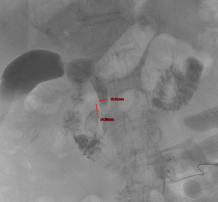

本次成功救治的两例患者,一例为胆总管中断恶性梗阻,另一例为胆总管下端结石嵌顿。面对肝内胆管不扩张的共同难题,我院介入团队果断采用了 “经皮经肝胆囊穿刺”这一技术路径。

1. 精准导航,一步到位:术前,通过磁共振胆管水成像(MRCP)精确绘制胆道“地图”,清晰显示梗阻部位与胆囊关系。术中,在超声实时引导下,采用经典的 Seldinger技术,犹如“穿针引线”,将穿刺针精准送入胆囊。值得一提的是,术中我们严格遵循安全路径,即经肝的右下周边穿刺,经胆囊床进入胆囊,此举有效避免了针道经过肝门等重要结构,相关并发症风险得以显著降低。 随后置入导丝、扩张通道、留置引流管,一步到位。

术中在超声实时引导下进 通过Seldinger技术建立胆囊、胆总管

行胆囊精准穿刺 至十二指肠的手术通道